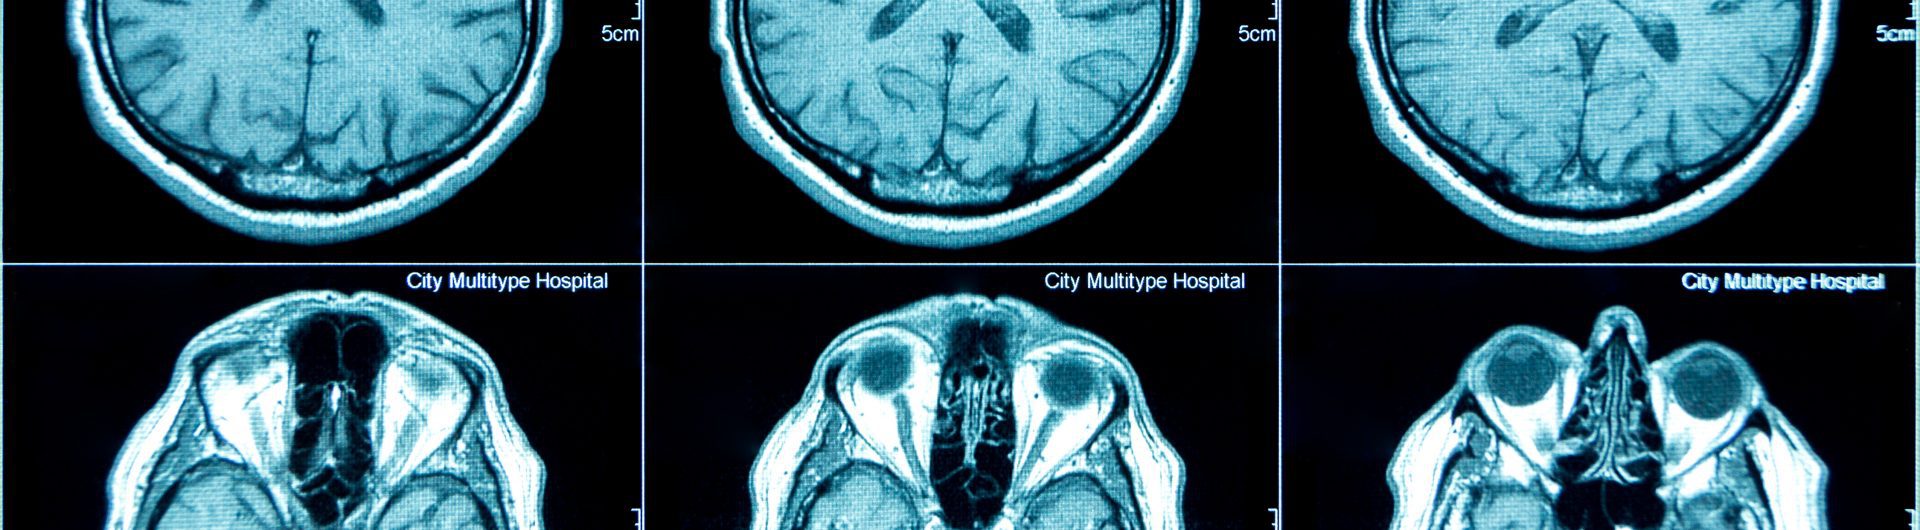

Motor vehicle accidents can leave victims with serious injuries, including the potential for a traumatic brain injury. Also called TBIs, traumatic brain injuries are often caused by motor vehicle accidents. Many people think about brain injuries as occurring from sports or even military injuries, but the truth is that auto accidents are also a major source of brain injury-related hospital visits. If you or a loved one suffered a brain injury in an auto accident due to someone else’s negligence, you need to contact a Rockford traumatic brain injury attorney.

The severity of your symptoms will provide medical professionals with some idea of the extent of your injuries. Diagnostic testing will need to be completed to confirm your traumatic brain injury.  Some potential symptoms include:

Treatment for brain injuries will vary based on the severity of the injury itself. Some injuries may resolve on their own with rest, while others will need invasive treatment like a decompressive craniectomy, in which a surgeon goes in to remove a section of the bone to relieve intracranial pressure.